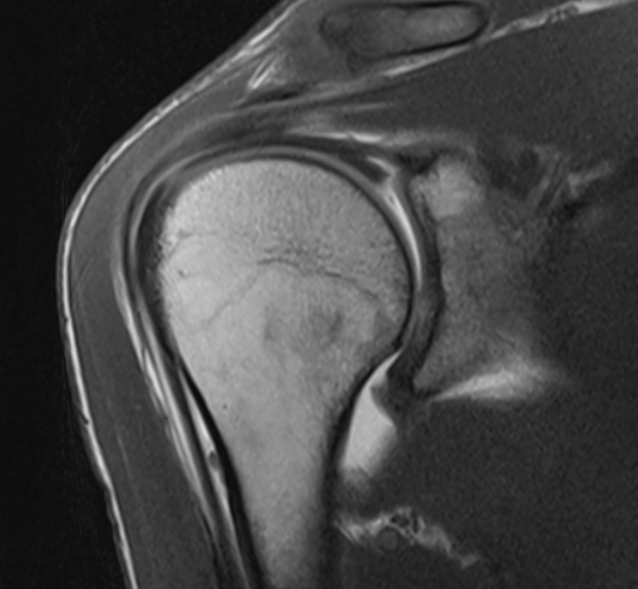

SLAP tear